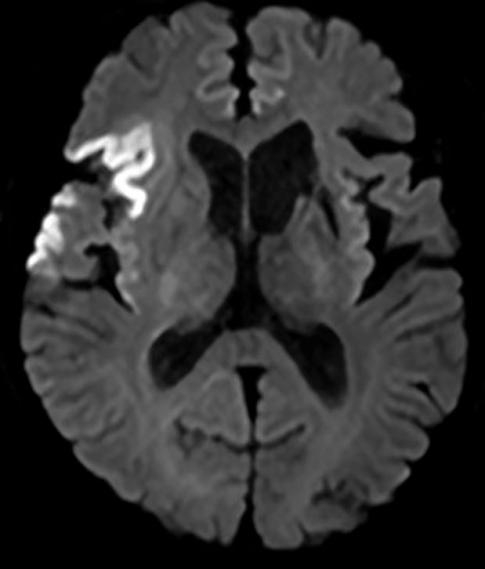

入院查体:神志清,精神一般,言语不清,双侧额纹对称,双侧瞳孔等大等圆,直径2.5 mm,对光反射灵敏,双侧鼻唇沟对称,口角左偏,左侧肢体肌力正常,右侧肢体肌力4级,指鼻试验阴性,生理反射存在,病理反射未引出,美国国立卫生研究院卒中量表NIHSS评分(National Institute of Health stroke scale, NIHSS)2分。入院诊断为急性脑梗死、高血压病3级(极高危)、陈旧性脑梗死。给予以阿司匹林联合氯吡格雷抗血小板,阿托伐他汀降脂稳定斑块,申捷营养神经等对症支持治疗。入院后进行头颅磁共振检查,提示右侧额顶颞叶、岛叶急性脑梗死,双侧大脑前动脉共左干,见图 1。经胸超声心动图提示:左心房增大,二尖瓣、三尖瓣轻度反流。颈动脉超声提示:双侧颈动脉内膜增厚伴左侧斑块形成(狭窄 < 50%)。椎动脉超声提示:声像图及多普勒血流频谱未见异常。自身抗体阴性。发泡试验结果为:强阳性,右向左分流(固有型,4级)。

| 右侧额顶颞叶、岛叶急性脑梗死 图 1 患者头颅磁共振DWI |